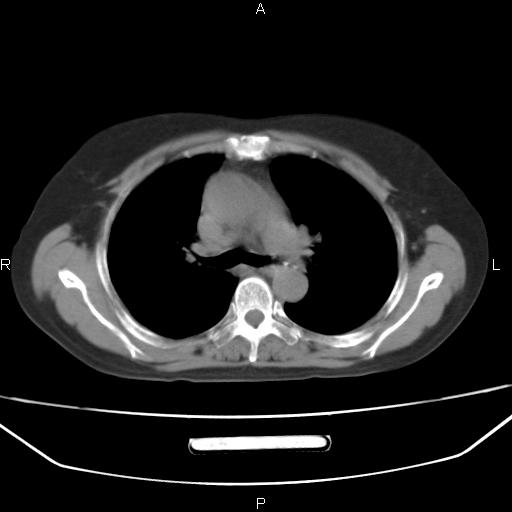

患者,女,66岁。健康体检胸部透视发现右上肺片状阴影。既往无不适,患者自诉三个月前曾有低热病史体温37.5左右一周。用药后缓解。至今无其它不适。请老师们指导指导。

考虑:右肺上叶周围型肺癌(分叶状肿块+砂粒状钙化+胸膜尾征)。

病灶见明显分叶、大小较大(大于3cm?),老年人,多考虑:肺癌,建议穿刺活检。

典型的中心型肺癌,尖段支气管阻塞。

以下是引用dyqct在2010-6-3 9:32:00的发言:[br]考虑:右肺上叶周围型肺癌(分叶状肿块+砂粒状钙化+胸膜尾征)。

不像中央型啊

右肺上叶周围型肺癌可能性大。

考虑:右肺上叶周围型肺癌